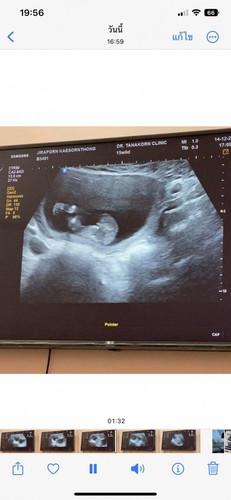

ซาวตอน 15w ค่ะหมอบอกว่ารอบหน้าจะชัดกว่านี้